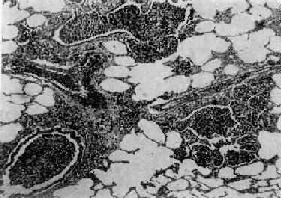

图9-19 支气管肺炎 图中见灶状实变的肺组织,肺泡内充满以中性粒细胞为主的炎性渗出物;病灶中有发炎的细支气管 【并发症】 小叶性肺炎发生并发症的危险性比大叶性肺炎大得多。可并发心力衰竭、呼吸衰竭、脓毒败血症、肺脓肿及脓胸等。支气管破坏较重且病程较长者,可导致支气管扩张。 【临床病理联系】 因小叶性肺炎多为其他疾病的并发症,其临床症状常为原发性疾病所掩盖。由于支气管粘膜的炎症刺激而引起咳嗽,痰呈粘液脓性。因病变常呈灶性散布,肺实变体征一般不明显。病变区细支管和肺泡内含有渗出物,听诊可闻湿啰音。X线检查,可见肺野内散在不规则小片状或斑点状模糊阴影。本病发现及时,治疗得当,肺内渗出物可完全吸收而痊愈。但在幼儿,年老体弱者,特别是并发于其他严重疾病时,预后大多不良。 (二)病毒性肺炎 病毒性肺炎(viral pneumonia)常常是因上呼吸道病毒感染向下蔓延所致。患者多为儿童,症状轻、重不等,但婴幼儿和老年患者病情较重。一般多为散发,偶可酿成流行。引起肺炎的病毒种类较多,常见的是流感病毒、还有呼吸道合胞病毒、腺病毒、副流感病毒、麻疹病毒、巨细胞病毒等等,也可由一种以上病毒混合感染并可继发细菌感染。病毒性肺炎的病情、病变类型及其严重程度常有很大差别。 【病理变化】 早期或轻型病毒性肺炎表现为间质性肺炎,炎症从支气管、细支气管开始,沿肺间质发展,支气管、细支气管壁及其周围、小叶间隔以及肺泡壁等肺间质充血、水肿,有一些淋巴细胞和单核细胞浸润,肺泡壁明显增宽(图9-20)。肺泡腔内一般无渗出物或仅有少量浆液。病变较重者,肺泡也可受累,出现由浆液、少量纤维蛋白、红细胞及巨噬细胞组成的炎性渗出物,甚至可发生组织坏死。有些病毒性肺炎(如流感病毒肺炎,麻疹病毒肺炎、腺病毒肺炎等)肺泡腔内渗出较明显,渗出物浓缩凝结成一层红染的膜样物贴附于肺泡内表面,即透明膜形成。支气管上皮的肺泡上皮也可增生,甚至形成多核巨细胞。麻疹病毒肺炎的病变特点为在间质性肺炎的基础上,肺泡壁上有透明膜形成,并有较多的多核巨细胞(巨细胞肺炎),在增生的上皮细胞和多核巨细胞的胞浆内和胞核内可检见病毒包含体。病毒包含体常呈球形,约红细胞大小,呈嗜酸性染色,均质或细颗粒状,其周围常有一清晰的透明晕。其他一些病毒性肺炎也可在增生的支气管上皮、支气管粘液腺上皮或肺泡上皮细胞内检见病毒包含体。如腺病毒肺炎可在增生的上皮细胞核内(图9-21),呼吸道合胞病毒肺炎可在增生的上皮细胞胞浆内,巨细胞病毒肺炎也可在增生的上皮细胞核内检见病毒包含体。检见包含体是病理组织学诊断病毒性肺炎的重要依据。

图9-17 肺肉质变 肺泡腔内炎性渗出物已被结缔组织所替代 (2)肺脓肿及脓胸或脓气胸:多见于由金黄色葡萄球菌引起的肺炎。 (3)纤维素性胸膜炎:是肺内炎症直接侵犯胸膜的结果。 (4)败血症或脓毒败血症:见于严重感染时,细菌侵入血流繁殖所致。 (5)感染性休克:严重的肺炎链球菌或金黄色葡萄球菌感染引起严重的毒血症时可发生休克,称休克型或中毒性肺炎,病死率较高。 【临床病理联系】 疾病发展过程中病变表现不一,临床体征也不相同。疾病早期时,主要病变是肺泡腔内浆液渗出,听诊可闻湿啰音,X线检查仅见肺纹理增深。肺实变时,由于肺泡膜面积减少,可出现肺泡通气和血流比例失调而影响换气功能,使肺静脉血不能充分氧合,患者乃出现紫绀或呼吸困难。渗出物中红细胞为肺泡巨噬细胞吞噬,崩解后形成含铁血黄素混入痰中,使痰呈铁锈色。痰中可检出“心衰细胞”。肺实变的体征是,肺泡呼吸音减弱或消失,出现支气管呼吸音,语音震颤增强,叩诊呈浊音。因常并发纤维素性胸膜炎,患者有胸痛,听诊可闻胸膜摩擦音。X线检查,可见大叶性或段性分布的均匀性密度增高阴影。病变消散时,渗出物溶解液化,肺部可闻及捻发音,X线表现为散在不均匀片状阴影,约在2~3周后阴影方完全消散。抗生素治疗,可缩短病程,减轻病变,合并症也大为减少。 2.小叶性肺炎 小叶性肺炎(lobular pneumonia)主要由化脓菌感染引起,病变起始于细支气管,并向周围或末梢肺组织发展,形成以肺小叶为单位、呈灶状散布的肺化脓性炎。因其病变以支气管为中心故又称支气管肺炎(bronchopneumonia)。主要发生于小儿和年老体弱者。 【病因和发病机制】 小叶性肺炎主要由细菌感染引起,常见的致病菌有葡萄球菌、链球菌、肺炎球菌、流感嗜血杆菌、绿脓杆菌和大肠杆菌等。这些细菌通常是口腔或上呼吸道内致病力较弱的常驻寄生菌,往往在某些诱因影响下,如患传染病、营养不良、恶病质、慢性心力衰竭、昏迷、麻醉、手术后等,使机体抵抗力下降,呼吸系统的防御功能受损,细菌得以入侵、繁殖,发挥致病作用,引起支气管肺炎。因此,支气管肺炎常是某些疾病的并发症,如所谓麻疹后肺炎、手术后肺炎、吸入性肺炎、坠积性肺炎等等。 【病理变化】 小叶性肺炎的病变特征是肺组织内散布一些以细支气管为中心的化脓性炎症病灶。常散布于两肺各叶,尤以背侧和下叶病灶较多。病灶大小不等,直径多在1cm左右(相当于肺小叶范围),形状不规则,色暗红或带黄色(图9-18)。严重者,病灶互相融合甚或累及全叶,形成融合性支气管肺炎(confluent bronchopneumonia)。镜下,病灶中支气管、细支气及其周围的肺泡腔内流满脓性渗出物,纤维蛋白一般较少(图9-19)。病灶周围肺组织充血,可有浆液渗出、肺泡过度扩张等变化。由于病变发展阶段的不同,各病灶的病变表现和严重程度亦不一致。有些病灶完全化脓,支气管和肺组织遭破坏,而另一些病灶内则可仅见浆液性渗出,有的还停留于细支气管及其周围炎阶段。